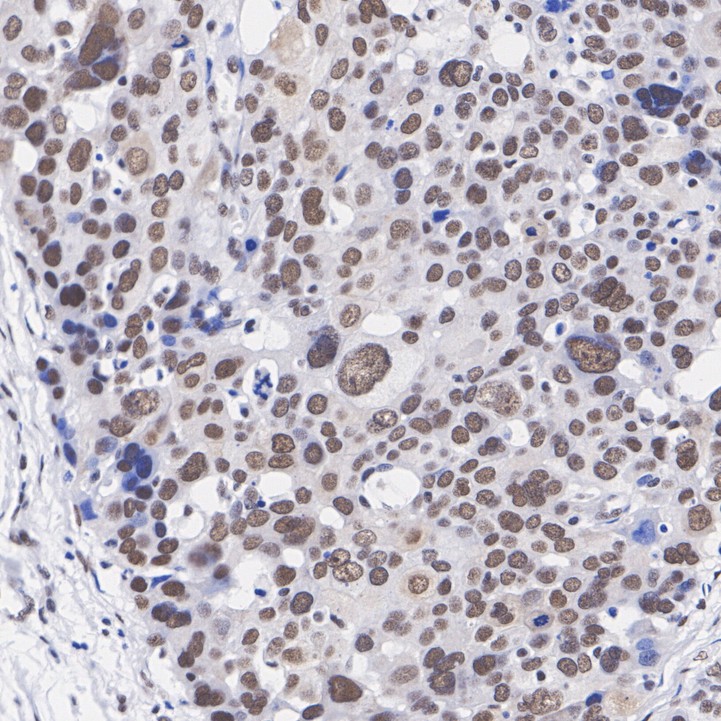

Immunohistochemical analysis of paraffin-embedded human ovary cancer tissue with Mouse anti-HDAC3 antibody (M1511-3) at 1/10,000 dilution.

The section was pre-treated using heat mediated antigen retrieval with Tris-EDTA buffer (pH 9.0) for 20 minutes. The tissues were blocked in 1% BSA for 20 minutes at room temperature, washed with ddH2O and PBS, and then probed with the primary antibody (M1511-3) at 1/10,000 dilution for 1 hour at room temperature. The detection was performed using an HRP conjugated compact polymer system. DAB was used as the chromogen. Tissues were counterstained with hematoxylin and mounted with DPX.